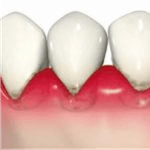

歯周病とは、磨き残しの中の歯周病菌が歯茎の周りで毒素を出すことによって歯茎が赤くなったり腫れたり、出血したり、そして「歯を支えているの顎の骨が溶ける病気」です。

歯周病の一歩手前、歯茎が赤く腫れている状態(歯肉炎)のうちは痛みも少なく自覚しにくいです。しかし、痛くないからといって放置をしていると、知らず知らずのうちに歯を支えている顎の骨が溶けていってしまいます(歯周炎・歯槽膿漏)。そして気付いた時には歯を支えている顎の骨がなくなり、歯はグラグラと揺れはじめ、物が噛めなくなったり最終的には歯が抜け落ちてしまう恐ろしい病気です。

歯周病とは、歯肉炎と歯周炎の総称です。歯茎にだけ炎症が起きている状態を「歯肉炎」と言い、歯肉炎が悪化して歯を支えている顎の骨にまで炎症が広がった状態を「歯周炎(歯槽膿漏)」と言います。

歯と歯茎の間には溝(歯周ポケット、歯肉溝)があり、健康な状態であれば歯周ポケットの深さは 1〜3ミリ以内で、歯茎はピンク色に引き締まっています。

・歯肉は赤く、腫れている

・歯磨きした時に出血する

・歯肉の退縮はなく、骨も溶けていない